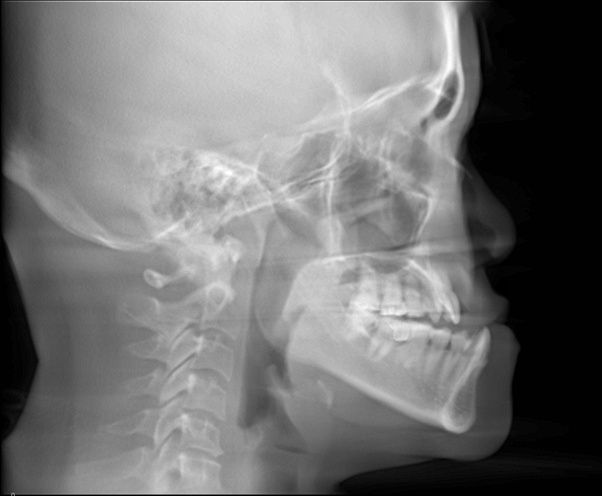

Class III malocclusion (more commonly referred to as an underbite or an anterior crossbite) affects approximately 10% of the population, where the lower jaw outgrows the upper jaw, causing the lower teeth to overlap the upper teeth. In a normal or ideal bite, the upper front teeth should slightly overlap the lower front teeth. Approximately 20 - 25 percent of our patients at Chatswood and St Ives Orthodontics seek treatment for an underbite.

Underbites often have a genetic origin and can be identified by excessive growth of the lower jaw, a smaller upper jaw, or a combination of both. These characteristic features typically manifest at an early age, sometimes as early as 4-5 years old. If left untreated, Class III malocclusion tends to worsen as the individual grows, and does not self-correct, often leading to the need for jaw orthognathic (jaw) surgery in adulthood. This is due to the fact that the lower jaw continues to grow forward for a longer period than the upper jaw.

In adults, correction of an underbite can vary depending on the severity of the malocclusion (misaligned bite) and their specific dental and skeletal needs. In mild cases, correction can be accomplished with braces, while more severe cases a combination of orthodontic treatment and orthognathic (jaw) surgery is necessary to achieve optimal results for adult Class III correction.